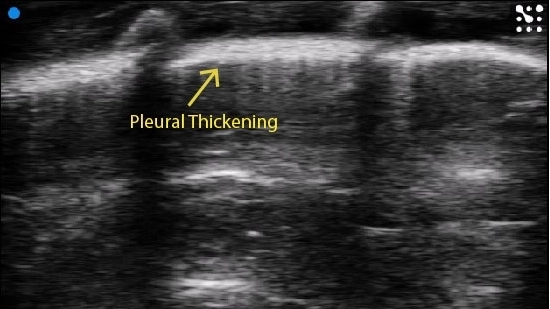

Pleural thickening can be observed.

Image courtesy of M.Sc. Niklas Hegemann, Kübler lab, Institute of Physiology, Charité-Universitätsmedizin Berlin & Dr. Jana Grune, Nahrendorf lab, Center for Systems Biology, Massachusetts General Hospital.